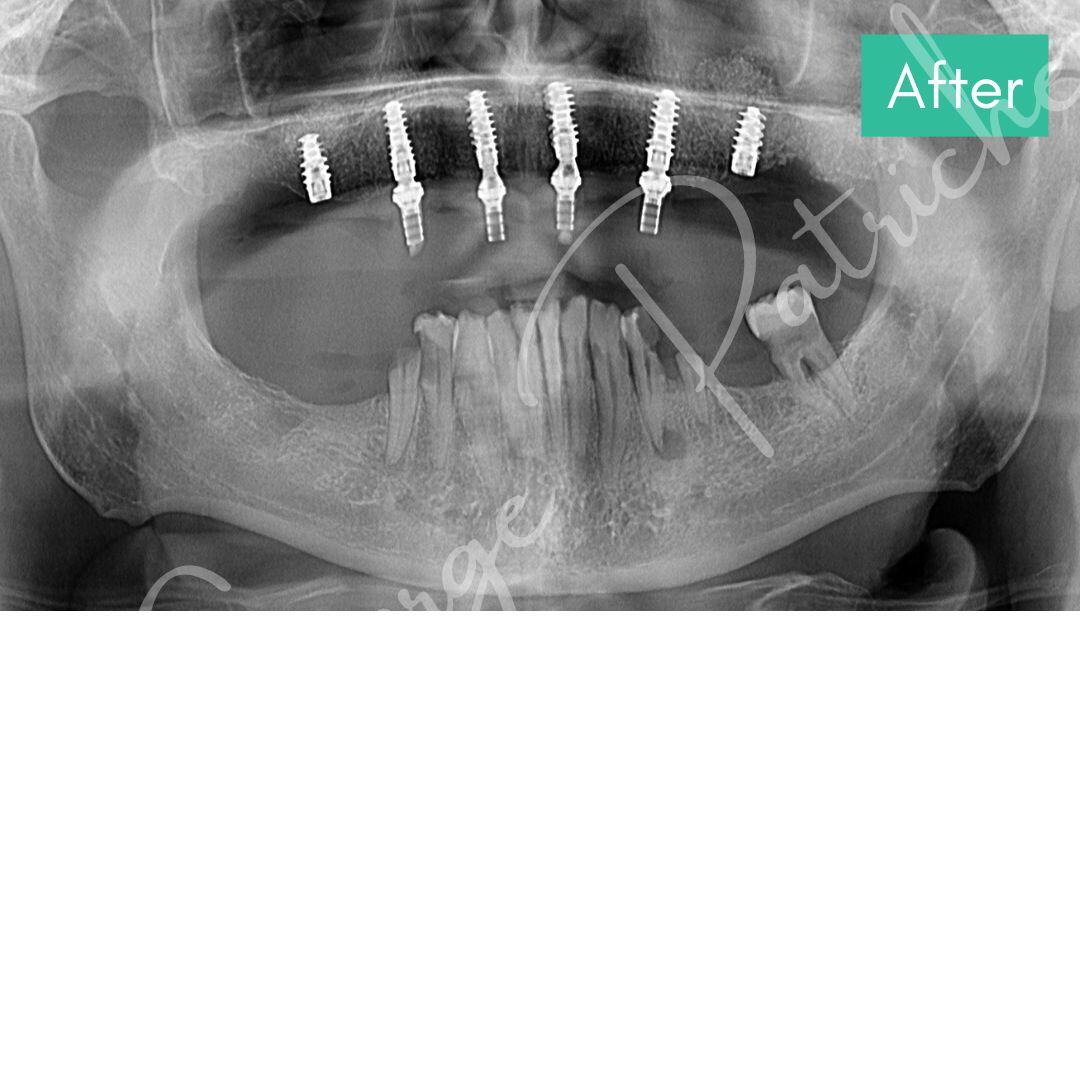

Before & After